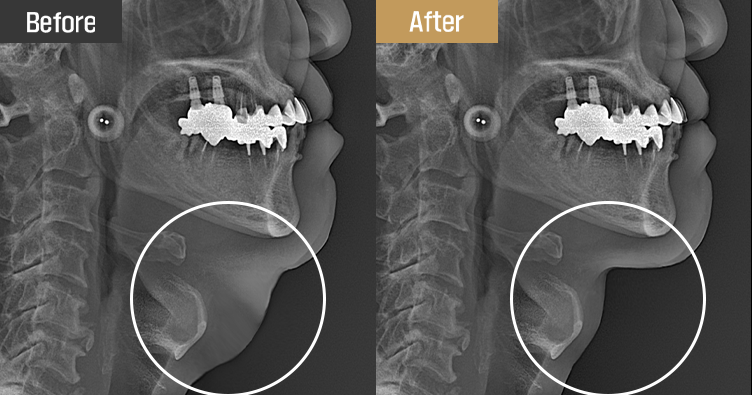

豊富な解剖学的知識を基に、

レントゲンと顔面超音波を利用して個人に合わせて計画を立てます。

脂肪の厚さと肌のたるみの程度、筋肉のたるみ、唾液腺肥大などを細かく把握し、

安全かつ確かな改善効果を提供します。

手術直後、レントゲンで効果をすぐに確認できます。